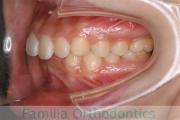

No.20V-496

- 叢生

- 年齢:

- 15歳

- 性別:

- 女性

- 抜歯部位

- 上:

- 84|58

- 下:

- 8558

全体的なでこぼこを治したいということで来院されました。上顎は右は4,左と下顎両側は5番を抜歯して、マルチブラケット法にて治療を行いました。2年強、25回程度の通院をしていただきました。

非常に強いでこぼこですので、後戻りのリスクは高めであると思われます。